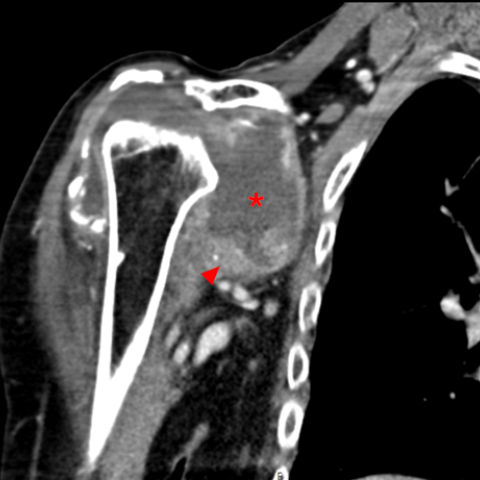

CT多平面重建软组织窗显示关节腔内存在大量积液(*),并伴有广泛的滑膜增生(箭头)。肩袖肌肉尤其是肩胛下肌明显脂肪浸润(五角星)。